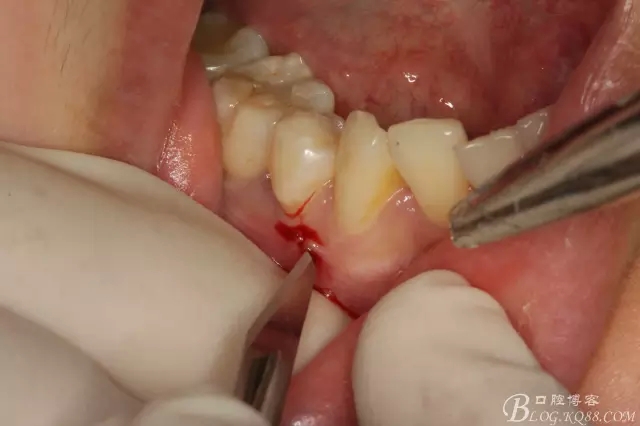

圖5.局部麻醉下、在44近中做垂直小切口,切口不要超過膜齦聯(lián)合。